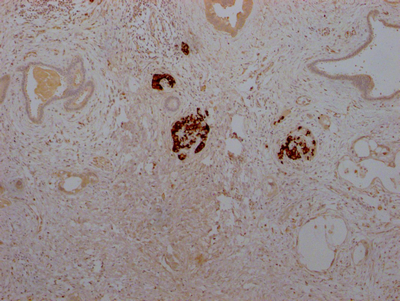

IHC image of CSB-RA584163A0HU diluted at 1:100 and staining in paraffin-embedded human pancreatic tissue performed on a Leica BondTM system. After dewaxing and hydration, antigen retrieval was mediated by high pressure in a citrate buffer (pH 6.0). Section was blocked with 10% normal goat serum 30min at RT. Then primary antibody (1% BSA) was incubated at 4℃ overnight. The primary is detected by a Goat anti-rabbit IgG polymer labeled by HRP and visualized using 0.05% DAB.

IHC image of CSB-RA584163A0HU diluted at 1:100 and staining in paraffin-embedded human pancreatic cancer performed on a Leica BondTM system. After dewaxing and hydration, antigen retrieval was mediated by high pressure in a citrate buffer (pH 6.0). Section was blocked with 10% normal goat serum 30min at RT. Then primary antibody (1% BSA) was incubated at 4℃ overnight. The primary is detected by a Goat anti-rabbit IgG polymer labeled by HRP and visualized using 0.05% DAB.